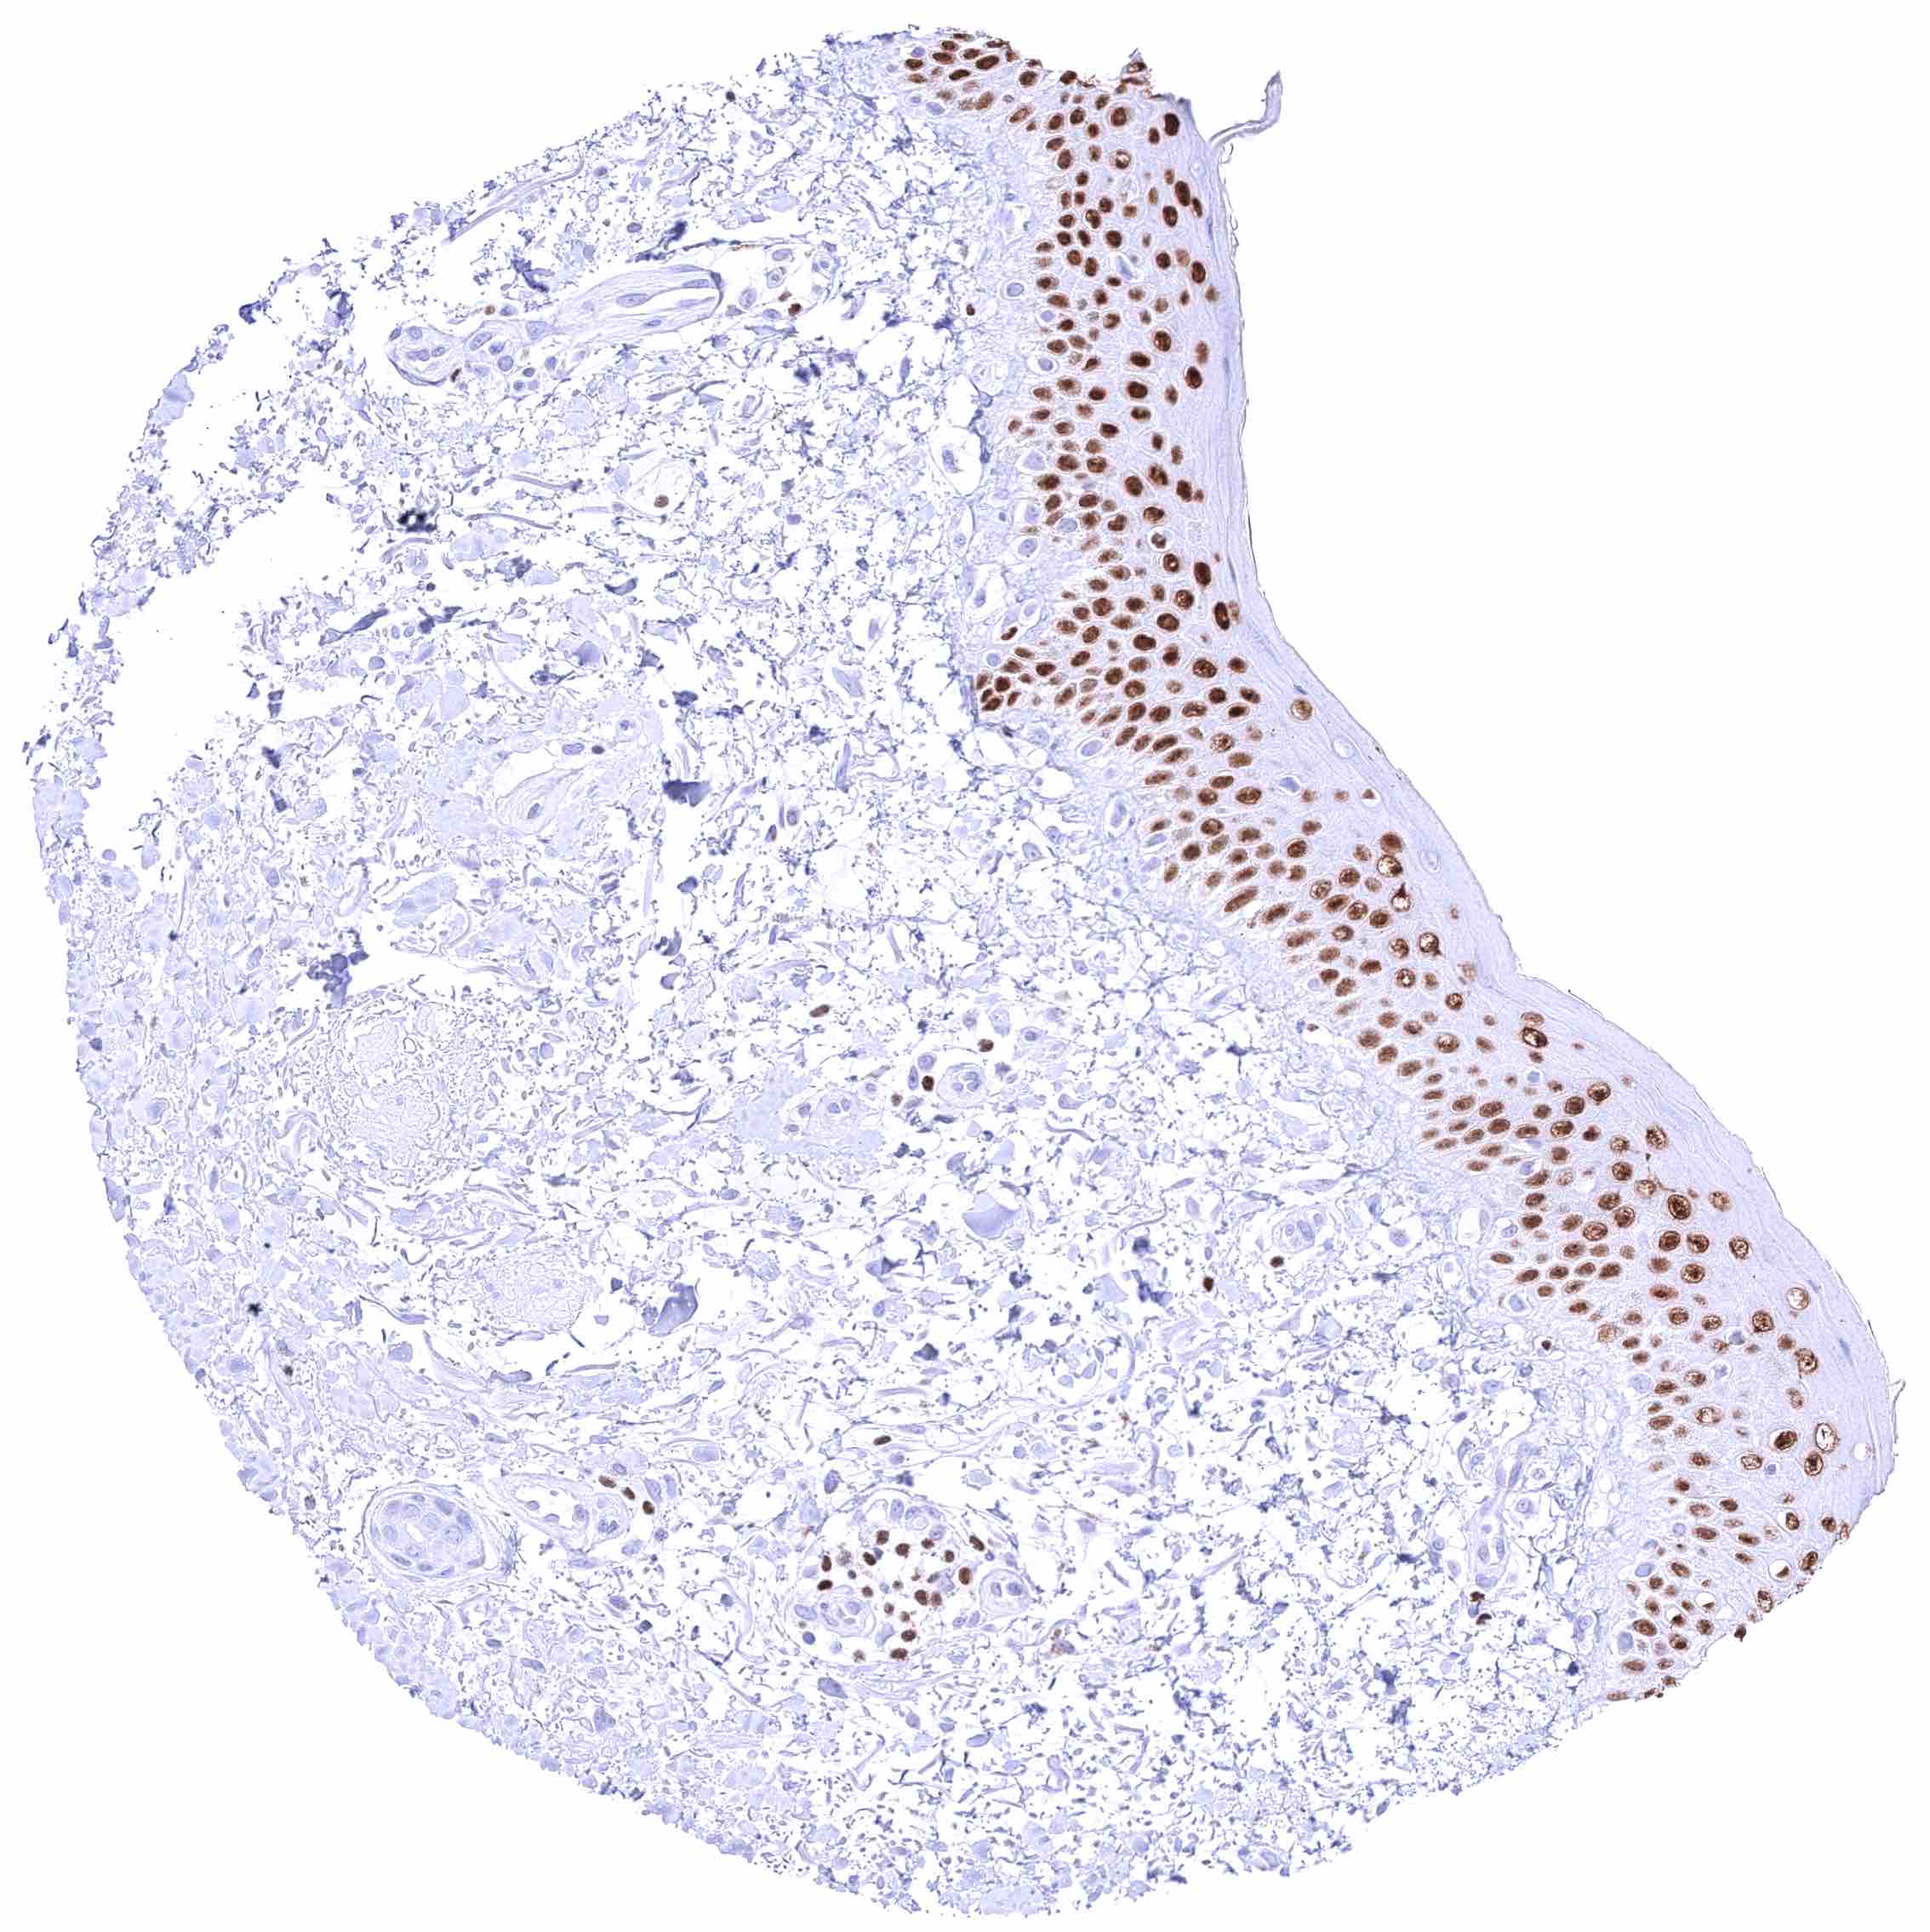

Skin – Strong nuclear GATA3 staining of squamous epithelial cells.

Skin, anal canal – Weak to moderate nuclear GATA3 staining of squamous epithelial cells. The staining predominates in the lower half of the epidermis.

Skin, hair follicel and sebaceous glands – Moderate nuclear GATA3 staining of cells of hair follicles and of peripheral germinative cells of sebaceous glands. GATA3 staining is faint or absent in cells of sebaceous glands.

Skin, hair follicel and sebaceous glands – Strong nuclear GATA3 staining of squamous epithelial cells, cells of hair follicles, and peripheral germinative cells of sebaceous glands. Nuclear GATA3 staining is faint or absent in cells of sebaceous glands.